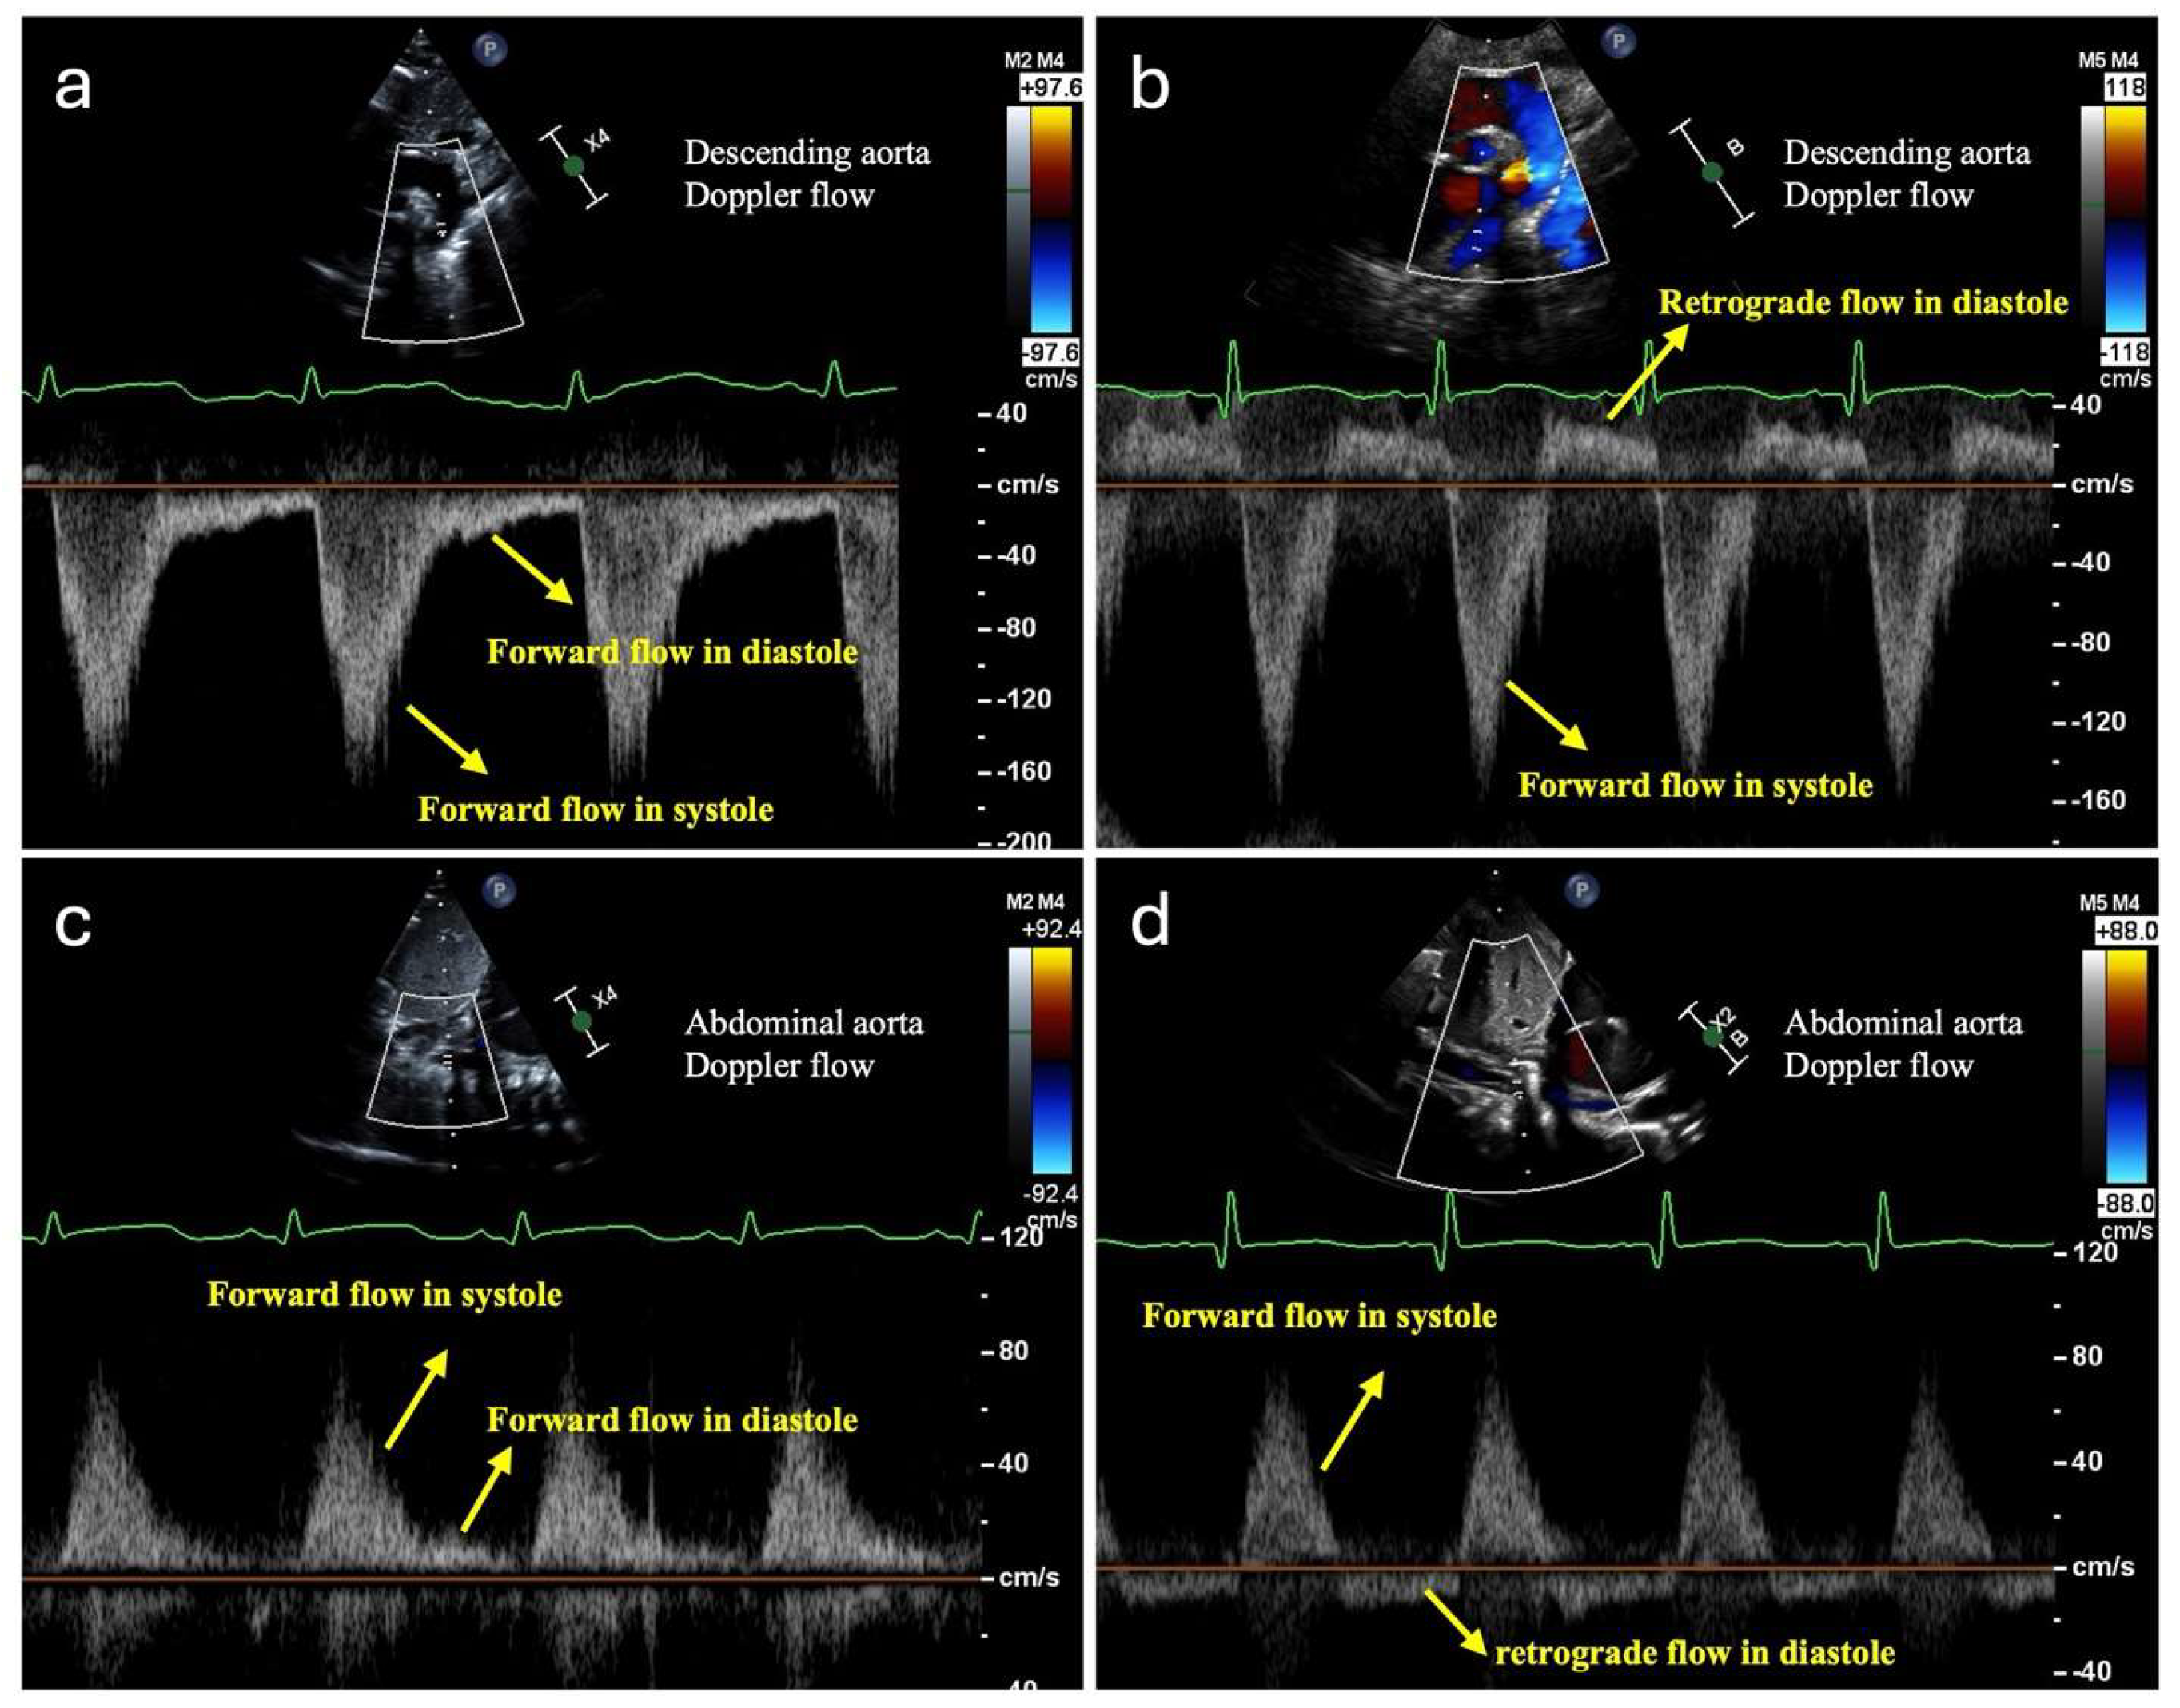

3.1. Monitoring Systemic Hypoperfusion and Hypoxia

3.2. Monitoring Pulmonary Overcirculation